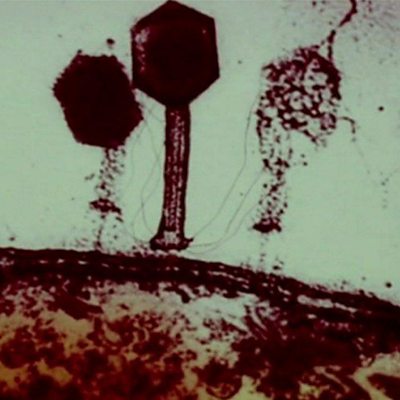

Bacteriophages in Georgia The subject of antibiotic resistance has been in the news this week with a warning coming from Britain’s Chief Medical Officer, Dame Sally Davies, that the threat from microbes becoming resistant to antibiotics should be ranked alongside terrorism and climate change. Phage therapy, where harmless viruses are used to kill the specific bacterium causing an infection, is a potential alternative. It is a treatment that has been used throughout the former USSR for the past 90 years and is becoming ever more popular, as the BBC’s Damien McGuinness reports from the Georgian capital Tbilisi. The Potential of Phage Therapy Research councils have begun putting more money into phage therapy and Dr Martha Clokie, Reader in Microbiology at Leicester University in the UK, is suddenly finding that scientific meetings on the subject are packed out. But critics say that so far the field has failed to deliver with very few trials having taken place, so could phage therapy really ever be a replacement for antibiotics? Fukushima Mental Health This week was the second anniversary of the tsunami, earthquake and disaster at the Fukushima nuclear power plant in Japan. Last year a survey of more than 200,000 people living in the area found that levels of extreme stress are three times the national average. Another survey this year is soon to be published, and will illustrate whether mental health has improved or deteriorated in that time. Meanwhile psychiatrists such as Yuriko Suzuki from the National Institute of Mental Health in Tokyo regularly visit the region. She tells us what help is being given. Health Myth Is it true that cheese gives you nightmares? Professor Matthew Walker is a neurologist at University College London. Picture credit: A bacteriophage attack on a bacteria, Eliava Institute, Tbilisi, Georgia